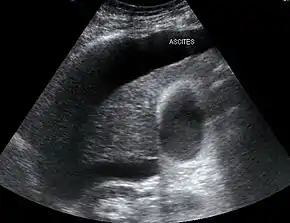

Those affect usually have cirrhosis, severe alcoholic hepatitis, or liver failure, with onset when liver function deteriorates rapidly because of a sudden insult such as an infection, bleeding in the gastrointestinal tract, or overuse of diuretics. Deteriorating liver function is believed to cause changes in the circulation that supplies the intestines, altering blood flow and blood vessel tone in the kidneys. The kidney failure of HRS is a consequence of these changes in blood flow, rather than direct damage to the kidney. Diagnosis is based on laboratory tests, Two types have been defined: type 1 entails a rapidly progressive decline in kidney function, while type 2 is associated with ascites (fluid accumulation in the abdomen) that does not improve with standard diuretics.

In contrast, type 2 HRS is slower in onset and progression, and is not associated with an inciting event. It is defined by an increase in serum creatinine level to >133 μmol/L (1.5 mg/dL) or a creatinine clearance of less than 40 mL/min, and a urine sodium < 10 μmol/L.[7] It also carries a poor outlook, with a median survival of approximately six months unless the affected individual undergoes liver transplantation. Type 2 HRS is thought to be part of a spectrum of illness associated with increased pressures in the portal vein circulation, which begins with the development of fluid in the abdomen (ascites). The spectrum continues with diuretic-resistant ascites, where the kidneys are unable to excrete sufficient sodium to clear the fluid even with the use of diuretic medications. Most individuals with type 2 HRS have diuretic-resistant ascites before they develop deterioration in kidney function.[8]

Both types of hepatorenal syndrome share three major components: altered liver function, abnormalities in circulation, and kidney failure. As these phenomena may not necessarily produce symptoms until late in their course, individuals with hepatorenal syndrome are typically diagnosed with the condition on the basis of altered laboratory tests. Most people who develop HRS have cirrhosis, and may have signs and symptoms of the same, which can include jaundice, altered mental status, evidence of decreased nutrition, and the presence of ascites.[2] Specifically, the production of ascites that is resistant to the use of diuretic medications is characteristic of type 2 HRS. Oliguria, which is a decrease in urine volume, may occur as a consequence of kidney failure; however, some individuals with HRS continue to produce a normal amount of urine.[3] As these signs and symptoms may not necessarily occur in HRS, they are not included in the major and minor criteria for making a diagnosis of this condition; instead HRS is diagnosed in an individual at risk for the condition on the basis of the results of laboratory tests, and the exclusion of other causes.[3]